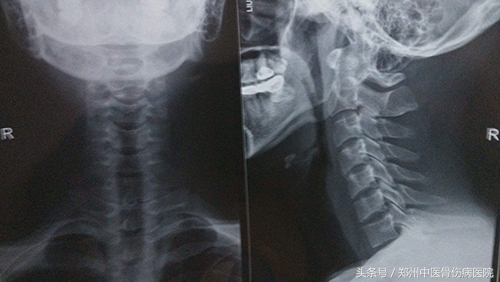

他抱着半信半疑的态度来到了郑州中医骨伤病医院。到院后,接诊他的是脊柱科的张其彬主任和王浩大夫。经过详细的沟通,及专科检查,拍摄颈椎五位片发现周先生环枢关节不对称,胸椎小关节紊乱并伴随有腰椎侧弯的问题。